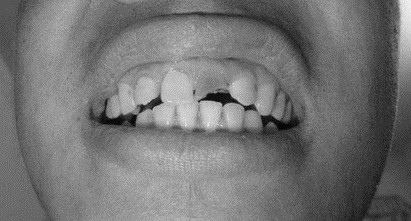

患者,男,38歲。上前牙變色1年,自述上前牙5年前受過外傷,唇側(cè)傾斜,檢查可見左上1牙冠變色,牙冠缺損近1/2,牙髓測試無反應(yīng),X線根尖片顯示患牙無明顯異常,全景片顯示雙側(cè)下頜智齒近中阻生,之前有發(fā)炎化膿病史,目前無咀嚼不適??谇黄溆酂o異常。

檢查情況及X線片見下圖:

(1)主訴診斷:左上1牙髓壞死(外傷)

(1)下前牙變色1年,下前牙5年前受過外傷,唇傾明顯。

(2)檢查見左上1牙冠變色,牙髓測試無反應(yīng),牙冠缺損近1/2,X線片無明顯異常。